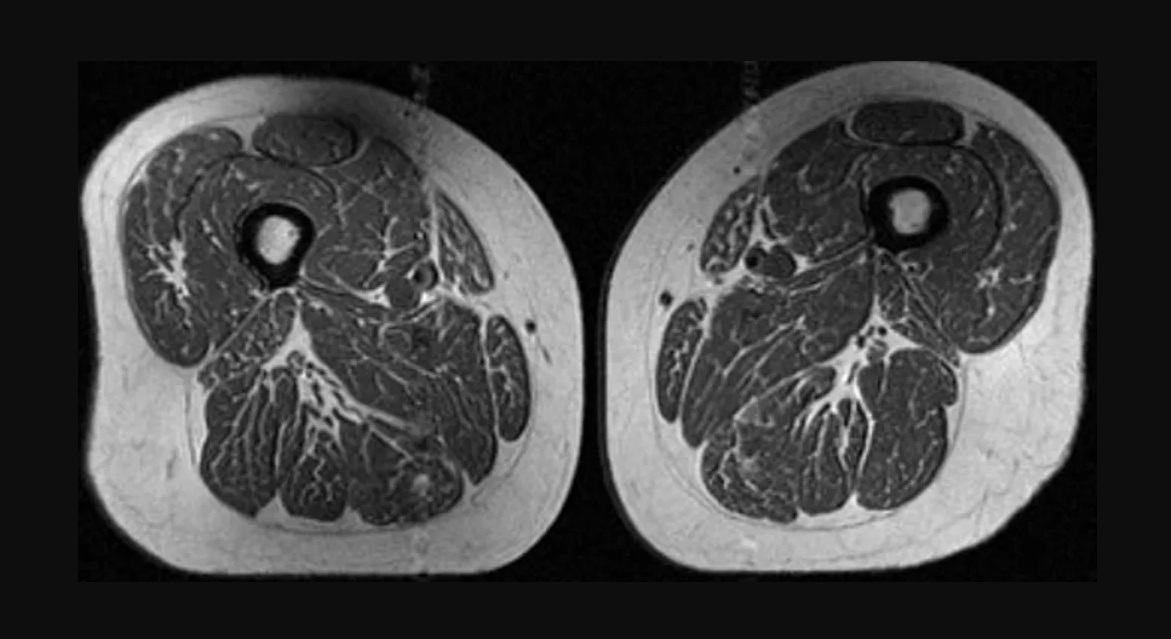

Un recent studiu a aruncat o lumină îngrijorătoare asupra consecințelor alimentației contemporane, punând în evidență faptul că un consum semnificativ de produse ultraprocesate este asociat cu acumularea de grăsime în masa musculară. Această descoperire, raportată de CNN, subliniază gravitatea problemelor de sănătate chiar și în rândul indivizilor care par sănătoși, fără afecțiuni evidente. De exemplu, o analiză RMN realizată pe o femeie care consuma alimente ultraprocesate în proporție de 87% a relevat modificări semnificative în structura mușchilor săi.

Studiul a implicat analiza a peste 600 de persoane și a scos în evidență o corelație preocupantă între o dietă bogată în suplimente ultraprocesate și creșterea grăsimii intramusculare. Imaginile RMN au arătat mușchi cu caracteristici asemănătoare „fripturilor marmorate”, datorită infiltrării grăsimii între fibrele musculare. Este notabil că acest proces a fost observat chiar și în cazul persoanelor care nu prezentau semne vizibile de osteoartrită, sugerând că degradarea calității musculare poate începe mult înainte de apariția simptomelor severe.